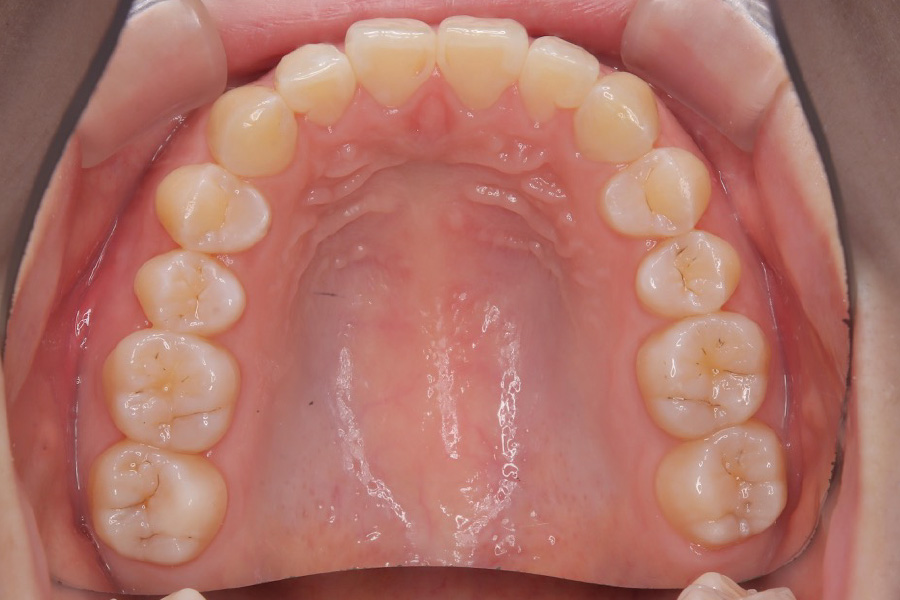

【20代女性】

歯の突出感、スペースを

インビザライン矯正で治療したケース

治療後

| 主訴 | 歯の突出感、スペースが気になる |

| 期間 | 2年半 |

| 費用 | 220,000円〜660,000円 (デンタルローン 3,100円〜6,600円/月) |

| 治療内容 | インビザライン矯正 非抜歯 |

| 治療に伴うリスク | 矯正終了後は、リテーナーを指示通りに使用し、歯の後戻りを防ぐ必要があります。 |